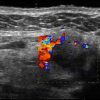

U tuyến nước bọt - Ảnh 4

U tuyến nước bọt

» Thông tin: Nữ giới – 60 tuổi.

» Lâm sàng: Khối vùng góc hàm.

# Di căn tuyến nước bọt dưới hàm.